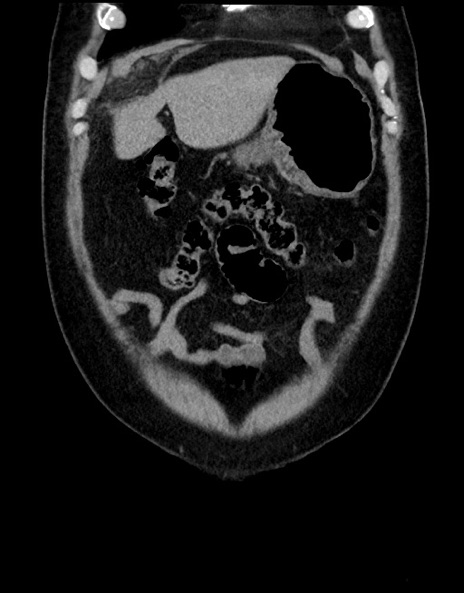

横断像

【症例】70歳代男性

【主訴】腹痛

【現病歴】今朝から腹痛あり。全体的に痛い。特に左上の方。排ガスが今日はない。冷や汗が出る。

【既往歴】直腸癌術後

【身体所見】左側腹部〜上腹部に圧痛あり。腹膜刺激症状明らかなではない。軽度反跳痛。左下腹部に術後瘢痕あり。

【データ】WBC 7700、CRP 0.02